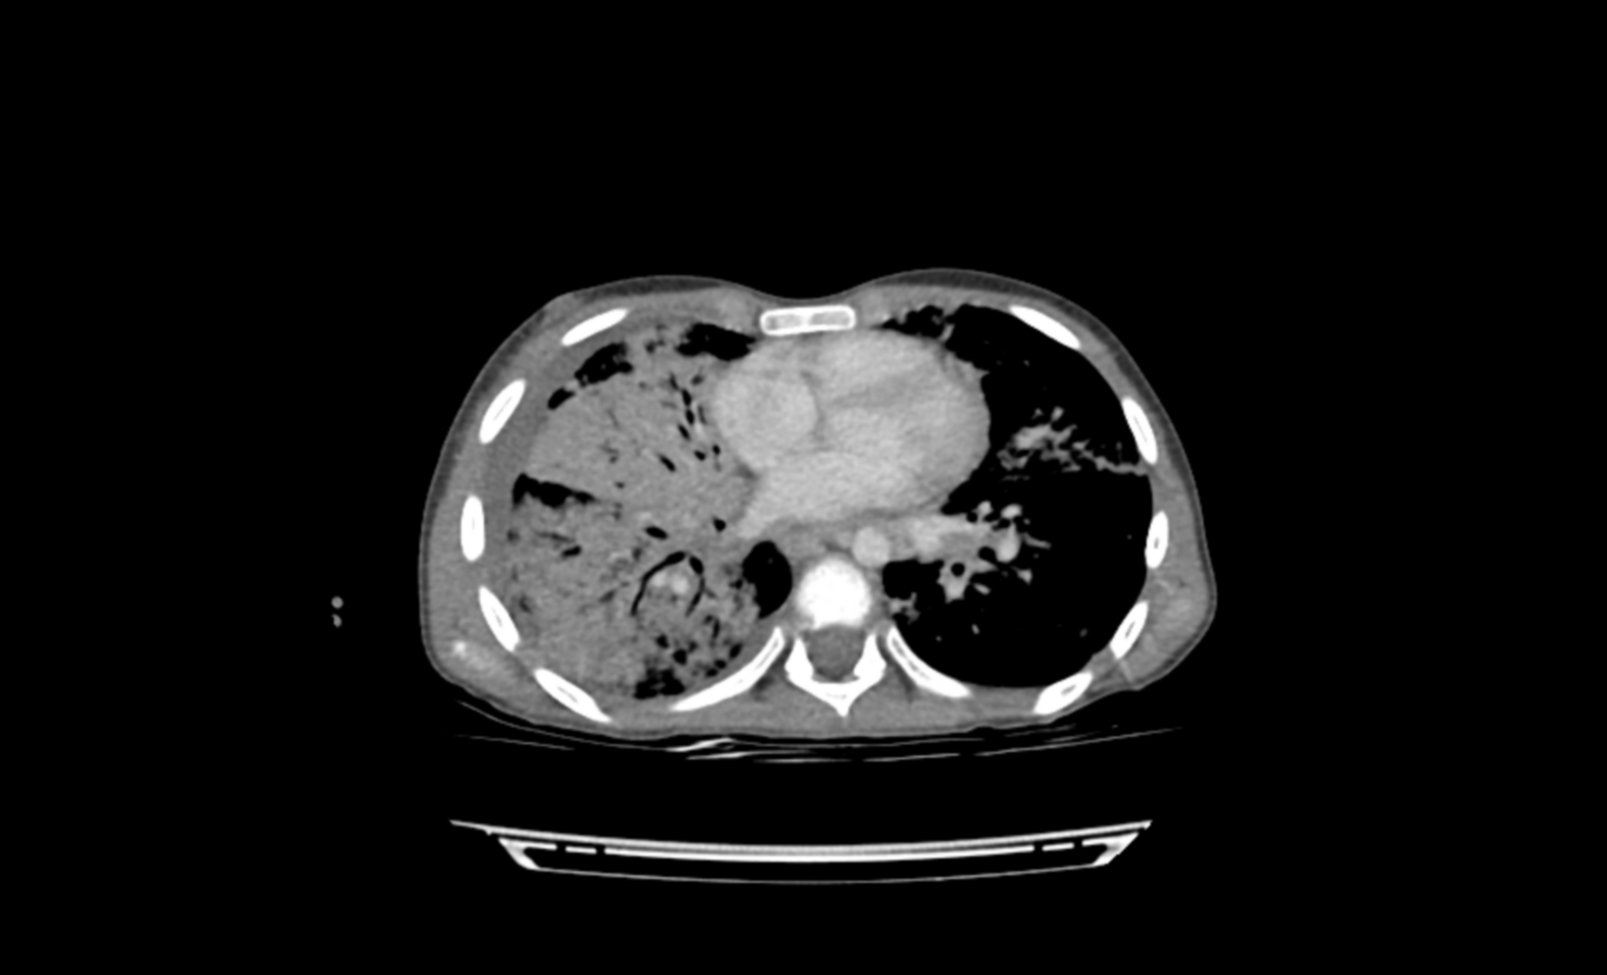

Ante la falta de etiología a filiar y la persistencia de astenia, anorexia, conglomerados adenopáticos y palpación de hepatomegalia, se decide solicitar una tomografía computarizada (TC) toraco-abdomino-pélvica.